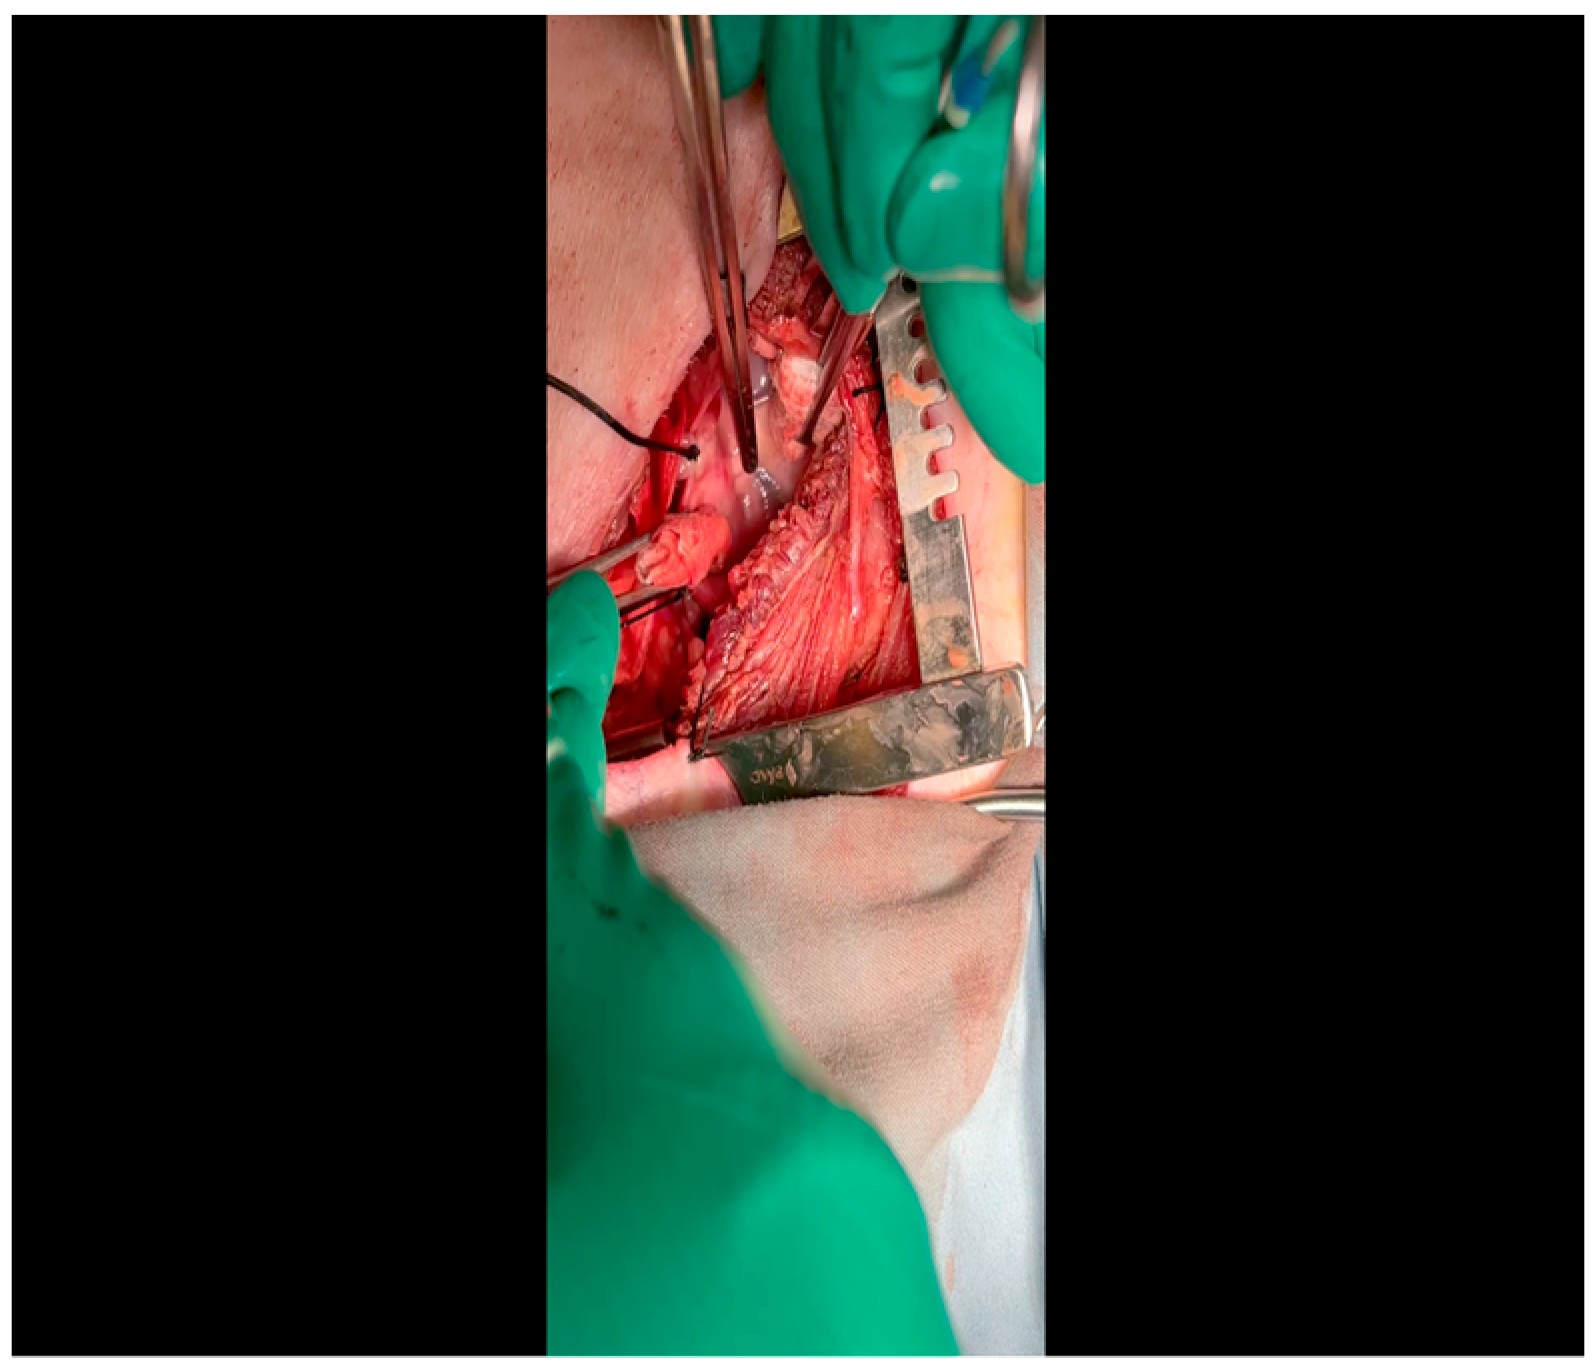

- Electrocautery is used to cut through the skin and muscle of the chest wall. A Weitlaner retractor is used to retract the muscle. The intercostal muscles are divided just above the 3rd or 4th rib (Figure 2), and a Kelly clamp facilitates entry into the parietal pleura and protects the underlying intrathoracic structures as the incision is enlarged; finally, a rib spreader is placed to open the incision.

- The pericardium is opened (Figure 3) with scissors. It is important to identify and protect the phrenic nerve.